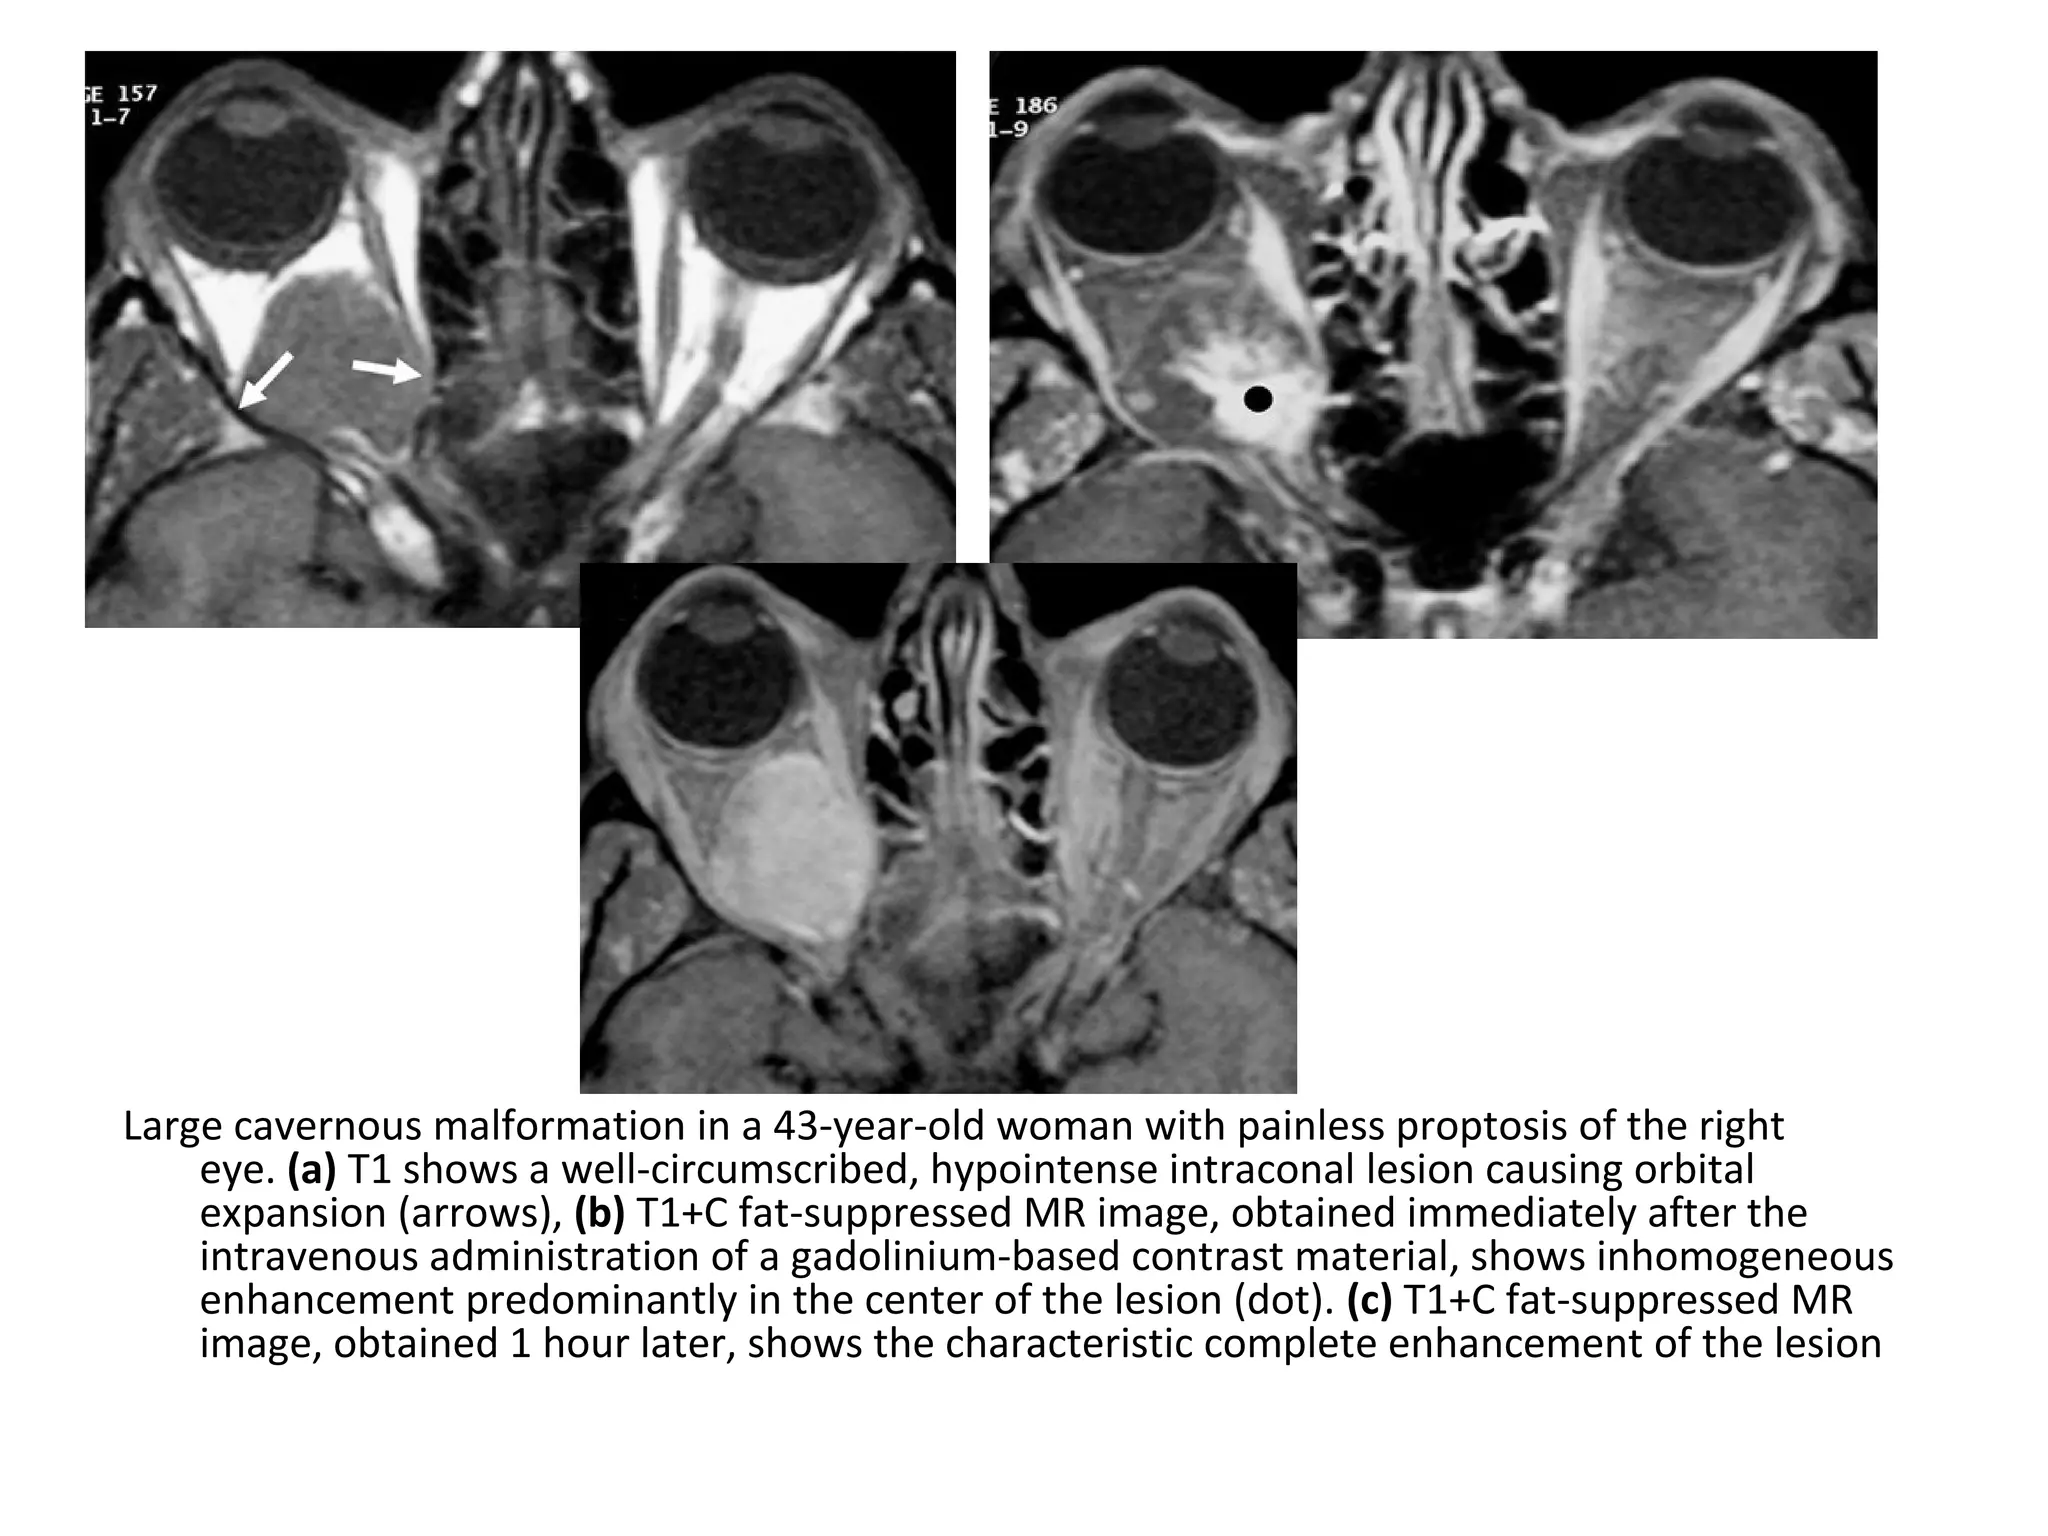

Large cavernous malformation in a 43-year-old woman with painless proptosis of the right

eye. (a) T1 shows a well-circumscribed, hypointense intraconal lesion causing orbital

expansion (arrows), (b) T1+C fat-suppressed MR image, obtained immediately after the

intravenous administration of a gadolinium-based contrast material, shows inhomogeneous

enhancement predominantly in the center of the lesion (dot). (c) T1+C fat-suppressed MR

image, obtained 1 hour later, shows the characteristic complete enhancement of the lesion